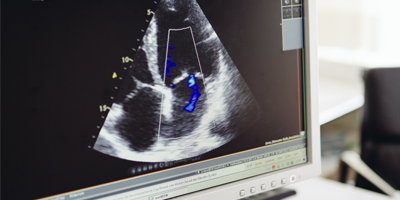

Die Herzinsuffizienz kann als Herzmuskelschwäche bezeichnet werden. Das Herz ist in diesem Fall nicht mehr in der Lage ausreichend Blut durch den Körperkreislauf zu pumpen. Die häufigste Ursache ist unter anderem eine Herzkranzgefäßerkrankung mit Minderdurchblutung des Herzens oder ein Bluthochdruck. Daneben gibt es auch Ursachen wie Herzmuskelentzündungen, genetische Veränderungen oder Herzklappenerkrankungen. Die Beschwerden hängen vom Ausmaß und vom Stadium der Herzschwäche ab und sind abhängig davon, ob der große oder kleine Herzkreislauf betroffen ist. Bei allen Formen der Herzschwäche ist ein frühzeitiges Erkennen und Behandeln entscheidend, um das Fortschreiten der Schwäche zu verzögern und die Leistungsfähigkeit und Vitalität zu erhalten.